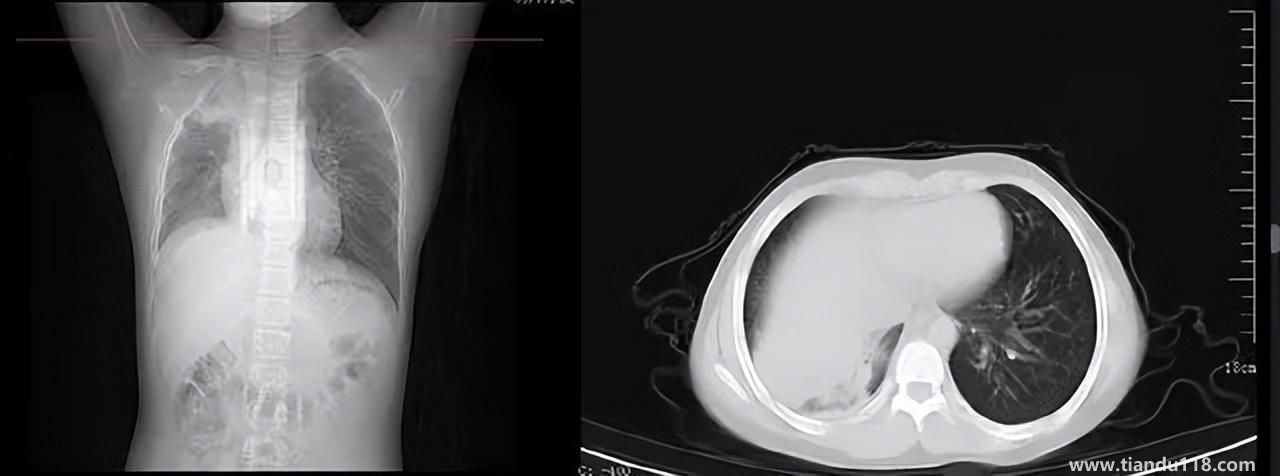

3個(gè)辦法可提前預(yù)警白肺(咋預(yù)防“白肺”) 3個(gè)辦法可提前預(yù)警白肺(咋預(yù)防“白肺”)家里有老人,擔(dān)心出現(xiàn)“大白肺”、“沉默型缺氧”等情況,具體如何應(yīng)對(duì),提前預(yù)警?近日,大象新聞接到諸多咨詢。針對(duì)這些問題,大象新聞?dòng)浾咦隽硕喾讲稍L。什么是白肺?對(duì)... 小編 2022-12-28 717

男孩咳嗽發(fā)熱在家硬扛成白肺(醫(yī)生表示以下幾種情況別硬“扛”) 男孩咳嗽發(fā)熱在家硬扛成白肺(醫(yī)生表示以下幾種情況別硬“扛”) 近日,一名12歲男孩咳嗽一周不就醫(yī),一側(cè)肺部“扛”成了“白肺”?!氨е鴥e幸心理一直在家硬‘扛’,沒想到‘扛’出這么重的??!”孩子家長(zhǎng)悔不... 小編 2022-12-28 967

為何有人出現(xiàn)“白肺”?專家回應(yīng)和疫苗接種無關(guān) 為何有人出現(xiàn)“白肺”?專家回應(yīng)和疫苗接種無關(guān)國(guó)務(wù)院聯(lián)防聯(lián)控機(jī)制12月27日召開新聞發(fā)布會(huì),針對(duì)有媒體提問稱,從近期公眾的反映情況看,有的新冠病毒感染者在就診過程中發(fā)現(xiàn)了肺炎或者是CT出現(xiàn)了“白肺”的現(xiàn)... 小編 2022-12-27 841

感染新冠會(huì)變白肺?醫(yī)生:有年輕病例 感染新冠會(huì)變白肺?醫(yī)生:有年輕病例感染新冠會(huì)變白肺嗎?對(duì)此,有專家表示,造成“白肺”情況有很多種,感染新冠只是一種可能。少量患者肺有滲液 ,咳嗽不會(huì)引發(fā)白肺,有年輕人病例。... 小編 2022-12-27 629